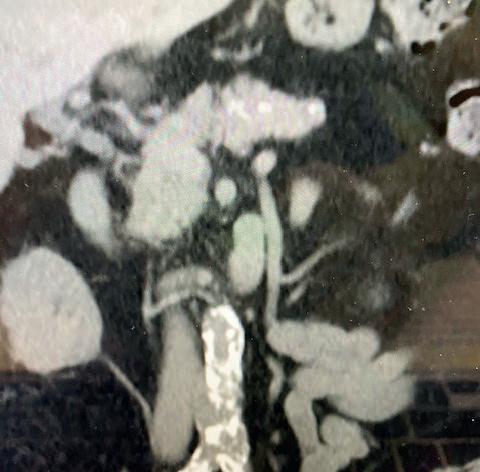

THE PATIENT IS AN 81-YEAR-OLD man with a past medical history of hypertension, hyperlipoproteinaemia, and remote history of smoking, who presents with an expanding saccular abdominal aortic aneurysm (AAA) and severe hip claudication. A preoperative computed tomography angiography (CTA) reveals dense circumferential calcified 90% stenosis of the bilateral common iliac arteries (Figures 1 and 2). In addition, the patient had a mid-aortic highly calcified stenosis. The patient desired a minimally invasive approach and given the underlying conditions, an EVAR was the best option to treat the AAA, as well as the bilateral common iliac artery stenosis.

Preoperative planning focused on three main areas of concern: the first is whether or not the stent graft could advance through the iliacs; secondly, would the stent graft limbs open to nominal diameter within the iliacs; and lastly, whether or not the stent graft would open fully within the AAA.

We used a percutaneous approach. Initially, we were unable to advance the 16Fr DrySeal sheath for the main graft on the right or the 12Fr DrySeal sheath on the left side for the contralateral limb (Figure 3). At this point, we performed IVL with a 7.0x60mm IVL catheter, of both the right and left common iliac arteries. We delivered 150 pulses to each vessel at 4atm and subsequently carefully dilated to nominal pressure of 6atm. Both arteries dilated easily. The Gore Excluder graft was delivered, and the limbs were placed within the common iliac arteries. Post-implantation balloon angioplasty was completed and revealed complete seal of the AAA and no residual stenosis in the iliacs (Figure 4). The patient was found to have a 90% stenosis of the left renal artery, which was treated with a balloon-expandable stent. His postprocedural CT scan revealed a very nice result, a sealed AAA, wide iliac arteries, and no residual stenosis.

Figure 3. Initial intraoperative angiogram

Figure 1. Preoperative CTA revealing dense calcified stenosis of the iliac bifurcation

common iliac luminal diameter of 3mm, left common iliac diameter of 5mm